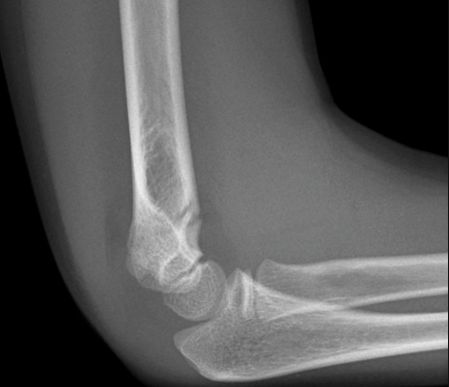

What is the most common paediatric elbow fracture? Which nerve and artery are most likely to be injured in this type of fracture?

Supracondylar fracture: often from fall on outstretched arm

Which nerve and artery can be damaged in a supracondylar fracture?